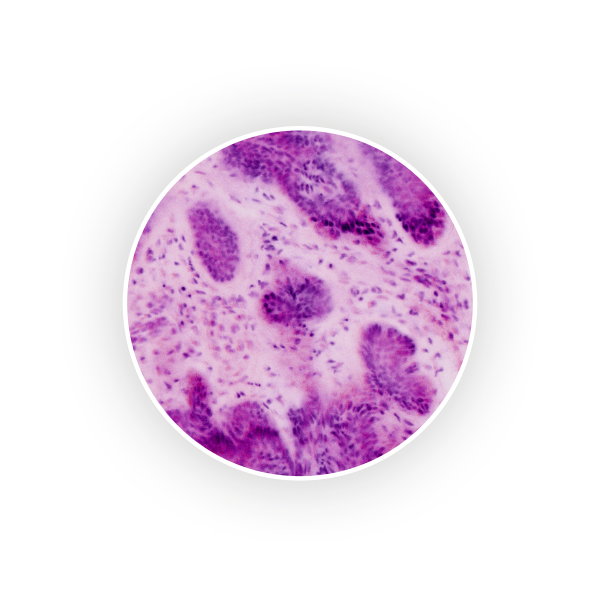

See every detail. Seamless zoom up to 550x. With a great sample size.

The VivaScope technology is based on confocal microscopy (CLSM) and acquires images of superb optical resolution and contrast. The VivaScope 2500 images allow seamless zoom with up to 500x magnification and a great sample size.

Image courtesy of Dr Javiera Pérez-Anker, Hospital Clinic of Barcelona.